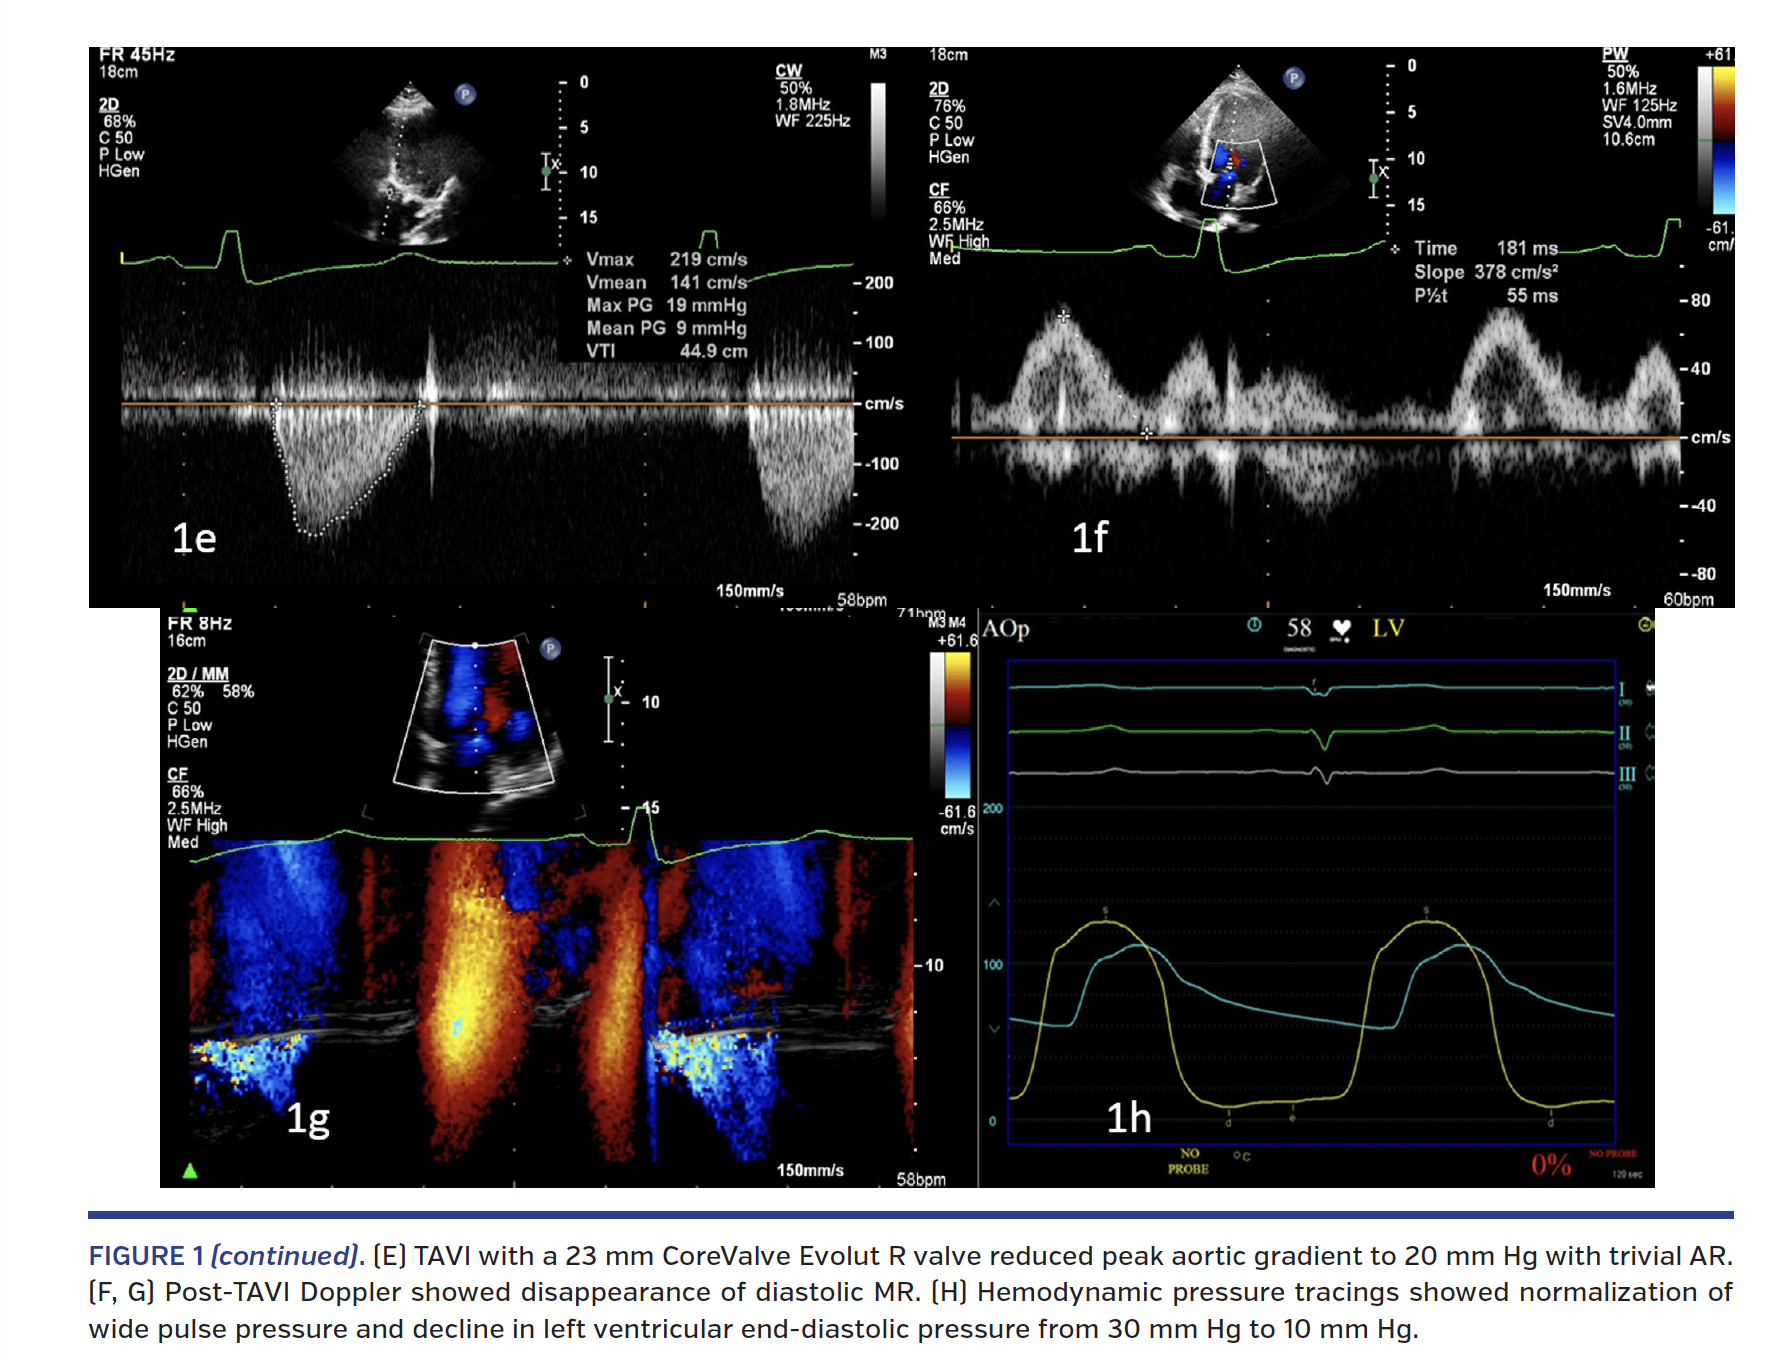

A 57-year-old gentleman was evaluated for symptomatic aortic bioprosthetic valve dysfunction 10 years after aortic valve replacement for aortic stenosis. Doppler echocardiography (Figure 1A) showed severe aortic regurgitation with pressure half-time of 170 ms and peak aortic gradient of 50 mm Hg. Mitral pulsed Doppler and color M-mode Doppler showed diastolic mitral regurgitation in the diastasis between the E and A waves (Figures 1B and 1C, blue arrows). Cardiac catheterization confirmed severe aortic regurgitation with elevation of left ventricular end-diastolic pressure (Figure 1D). Transcatheter aortic valve implantation (TAVI) with a 23 mm CoreValve Evolut R self-expanding valve (Medtronic) reduced the peak aortic gradient to 20 mm Hg with trivial aortic regurgitation (Figure 1E). Post-TAVI Doppler evaluation showed disappearance of diastolic mitral regurgitation (Figures 1F and 1G). Hemodynamic pressure tracings showed normalization of wide pulse pressure and decline in left ventricular end-diastolic pressure from 30 mm Hg to 10 mm Hg (Figure 1H).

Transient elevation of left ventricular diastolic pressure above left atrial pressure can occur in severe aortic regurgitation in the diastasis phase, reflected as the flow reversal at the end of the mitral propagation E wave. This also may be associated with a relatively abrupt deceleration of the E wave as the diastolic mitral regurgitation may eschew part of mid-diastolic inflow to the left ventricle. Post thoracotomy pericardial restraint and persistent left ventricular hypertrophy could also have contributed to the elevation of left ventricular end-diastolic pressure in this patient besides severe aortic regurgitation. The recognition of mitral E wave reversal in such a situation could serve as non-invasive evidence of elevated left ventricular diastolic pressures, thereby guiding therapeutic decision making.